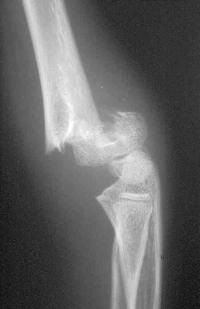

Radiographie

On demande une radiographie du coude Face et Profil

Le trait est transversal, extra-articulaire.

En fonction de l’importance du déplacement, on détermine le type de la fracture (classification de Lagrange et Rigault) :

- Stade 1 : fracture non déplacée, seule la corticale antérieure est touchée

- Stade 2 : bascule postérieure peu importante, les 2 corticales sont rompues

- Stade 3 : bascule importante mais les 2 fragments restent en contact

- Stade 4 : bascule importante, les 2 fragments ont perdu tout contact